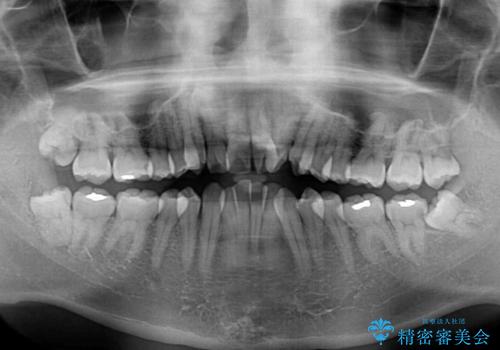

- 前歯のデコボコを気にして来院された患者様です。

叢生の解消とともに、前方に張り出した上顎前歯を引っ込めることを目的とし、上下左右の第一小臼歯4歯を抜歯をしてワイヤー矯正により治療することとしました。